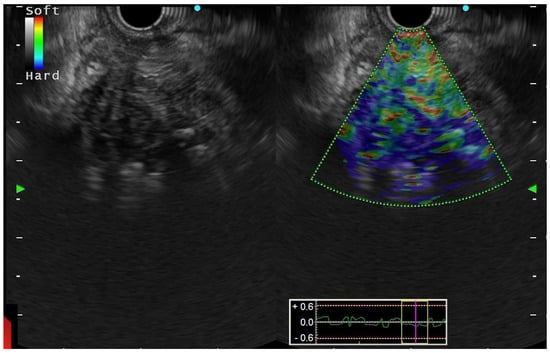

- Giovannini, M.; Hookey, L.C.; Bories, E.; Pesenti, C.; Monges, G.; Delpero, J.R. Endoscopic Ultrasound Elastography: The First Step towards Virtual Biopsy? Preliminary Results in 49 patients. Endoscopy 2006, 38, 344–348. [Google Scholar] [CrossRef] [PubMed]

- Giovannini, M.; Botelberge, T.; Bories, E.; Pesenti, C.; Caillol, F.; Esterni, B.; Monges, G.; Arcidiacono, P.; Deprez, P.; Yeung, R.; et al. Endoscopic ultrasound elastography for evaluation of lymph nodes and pancreatic masses: A multicenter study. World J. Gastroenterol. 2009, 15, 1587–1593. [Google Scholar] [CrossRef]

- Iglesias-García, J.; Lariño-Noia, J.; Abdulkader, I.; Forteza, J.; Domínguez-Muñoz, J.E. EUS-elastography for the characterization of solid pancreatic masses. Gastrointest. Endosc. 2009, 70, 1101–1108. [Google Scholar] [CrossRef]

- Hirche, T.O.; Ignee, A.; Barreiros, A.P.; Schreiber-Dietrich, D.; Jungblut, S.; Ott, M.; Hirche, H.; Dietrich, C.F. Indications and limitations of endoscopic ultrasound elastography for evaluation of focal pancreatic lesions. Endoscopy 2008, 40, 910–917. [Google Scholar] [CrossRef]

- Iglesias–Garcia, J.; Larino–Noia, J.; Abdulkader, I.; Forteza, J.; Dominguez–Munoz, J.E. Quantitative endoscopic ultrasound elastography: An accurate method for the differentiation of solid pancreatic masses. Gastroenterology 2010, 139, 1172–1180. [Google Scholar] [CrossRef]

- Săftoiu, A.; Iordache, S.A.; Gheonea, D.I.; Popescu, C.; Maloş, A.; Gorunescu, F.; Ciurea, T.; Iordache, A.; Popescu, G.L.; Manea, C.T. Combined contrast-enhanced power Doppler and real-time sonoelastography performed during EUS, used in the differential diagnosis of focal pancreatic masses (with videos). Gastrointest. Endosc. 2010, 72, 739–747. [Google Scholar] [CrossRef]

- Mei, M.; Ni, J.; Liu, D.; Jin, P.; Sun, L. EUS elastography for diagnosis of solid pancreatic masses: A meta-analysis. Gastrointest. Endosc. 2013, 77, 578–589. [Google Scholar] [CrossRef]

- Dietrich, C.F.; Hirche, T.O.; Ott, M.; Ignee, A. Real-time tissue elastography in the diagnosis of autoimmune pancreatitis. Endoscopy 2009, 41, 718–720. [Google Scholar] [CrossRef]